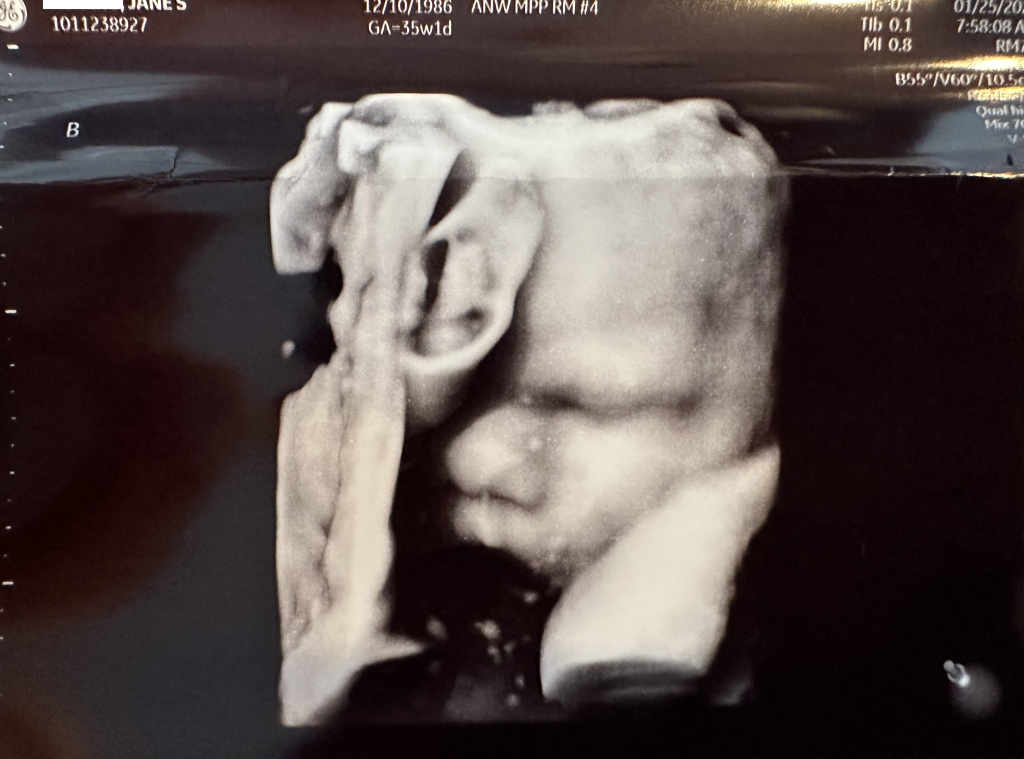

The entire team at Children’s has been more than amazing to work with and we just had our weekly checkup with them today. We are at 35 weeks and 1 day today, Luna is weighing in at 5lbs 6oz and Leo is at 6lbs 0oz, both doing great and on track for growth! Luna is still breech, but today Leo was cephalic… Jane has mentioned they both have been very very active at night, so there is still a chance Luna could flip around yet. Just in case, they had us schedule our C-section today which would take place on Feb 15th in the event they don’t come earlier.